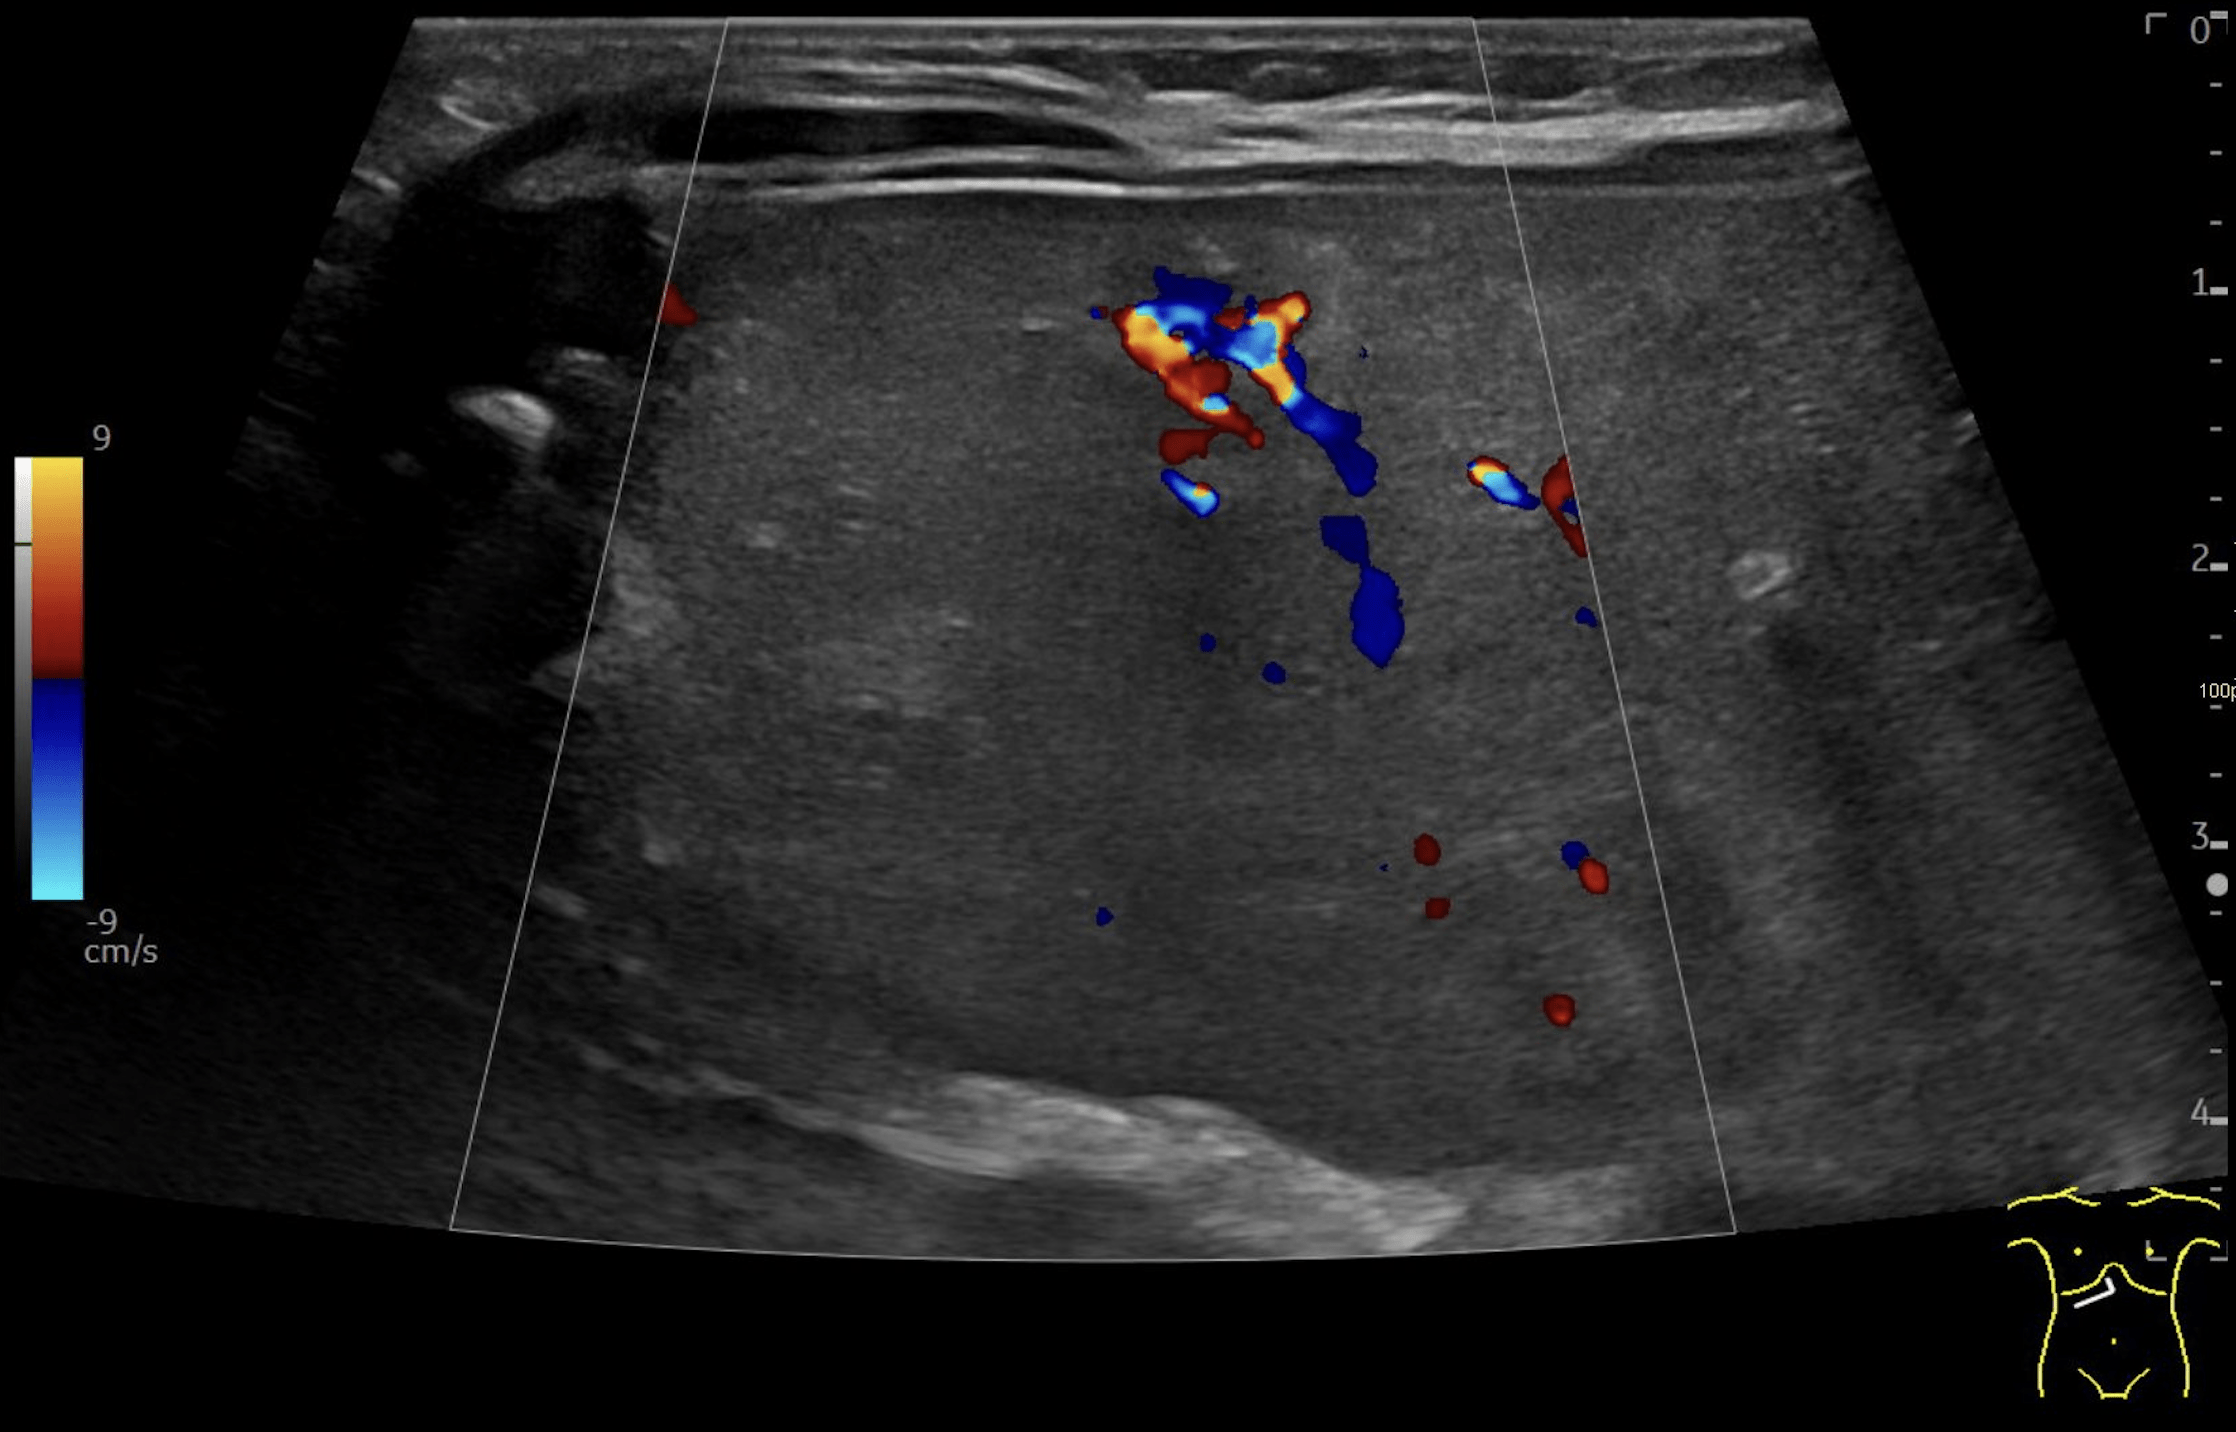

B: Doppler image of capillary hemangioma located ventrally in the right hepatic lobe, demonstrating large, tortuous vessels suggestive of possible arteriovenous shunting.

Multiple hepatic lesions were identified on ultrasound (A). Some lesions appeared as typical, well-defined hyperechoic cavernous hemangiomas (2), while others demonstrated large, tortuous vessels. Additional lesions showed a hyperechoic rim with a hypoechoic center and internal Doppler flow, consistent with capillary hemangiomas (2). In some HH (B), arteriovenous shunting was suspected. However, Triplex Doppler examination demonstrated normal hepatoportal flow in the portal vein (C) with flow velocities below 40 cm/s – within the normal range for the age – as well as a normal triphasic flow pattern in the hepatic veins (D).

In the present case, multiple hemangiomas – both cavernous and capillary subtypes - were detected in both liver and spleen. Some of the hepatic lesions demonstrated features suggestive of arteriovenous shunting.